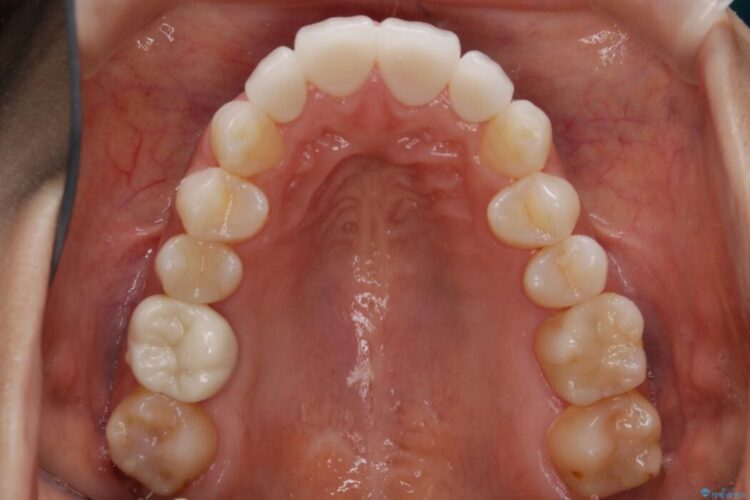

軽度のガタつきと不正咬合が見受けられましたので、インビザラインでの矯正治療を計画しました。

また確認したところ前歯と奥歯にセラミッククラウンで治療した歯があったため、そちらに影響のない範囲内で口腔内全体の噛み合わせが改善されるように歯を動かしていくことになりました。

既定のインビザラインの装着時間を守っていただけたこともあり整ったアーチとなりました。

本症例ではセラミッククラウンのかぶせ物をした歯が複数ありました。

セラミック等の被せ物がある場合、それ自体の外形は矯正治療では変えられないため天然歯の移動に影響を与えてしまうことがあります。